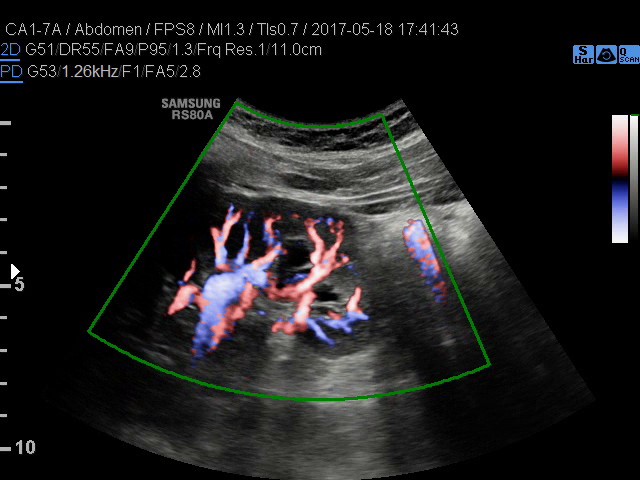

• USG doppler naczyń

kończyn górnych i dolnych - żylnych lub tętniczych

• USG doppler tętnic kończyn górnych i dolnych

• USG doppler aorty i naczyń biodrowych

• USG doppler układu wrotnego

Rozszerzamy ofertę naszych pracowni:

• diagnostyka NADCIŚNIENIA WROTNEGO - badanie śledziony